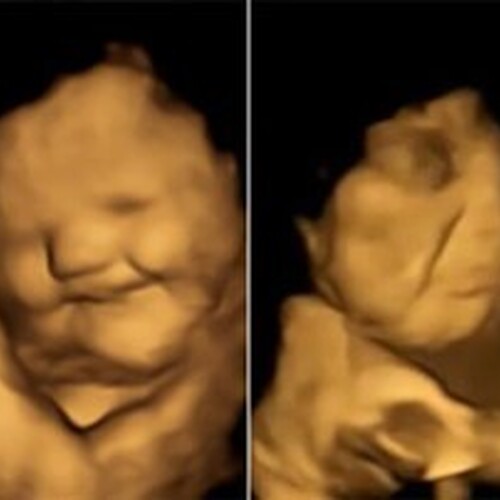

Proeven vóór je geboorte, 30 september 2025